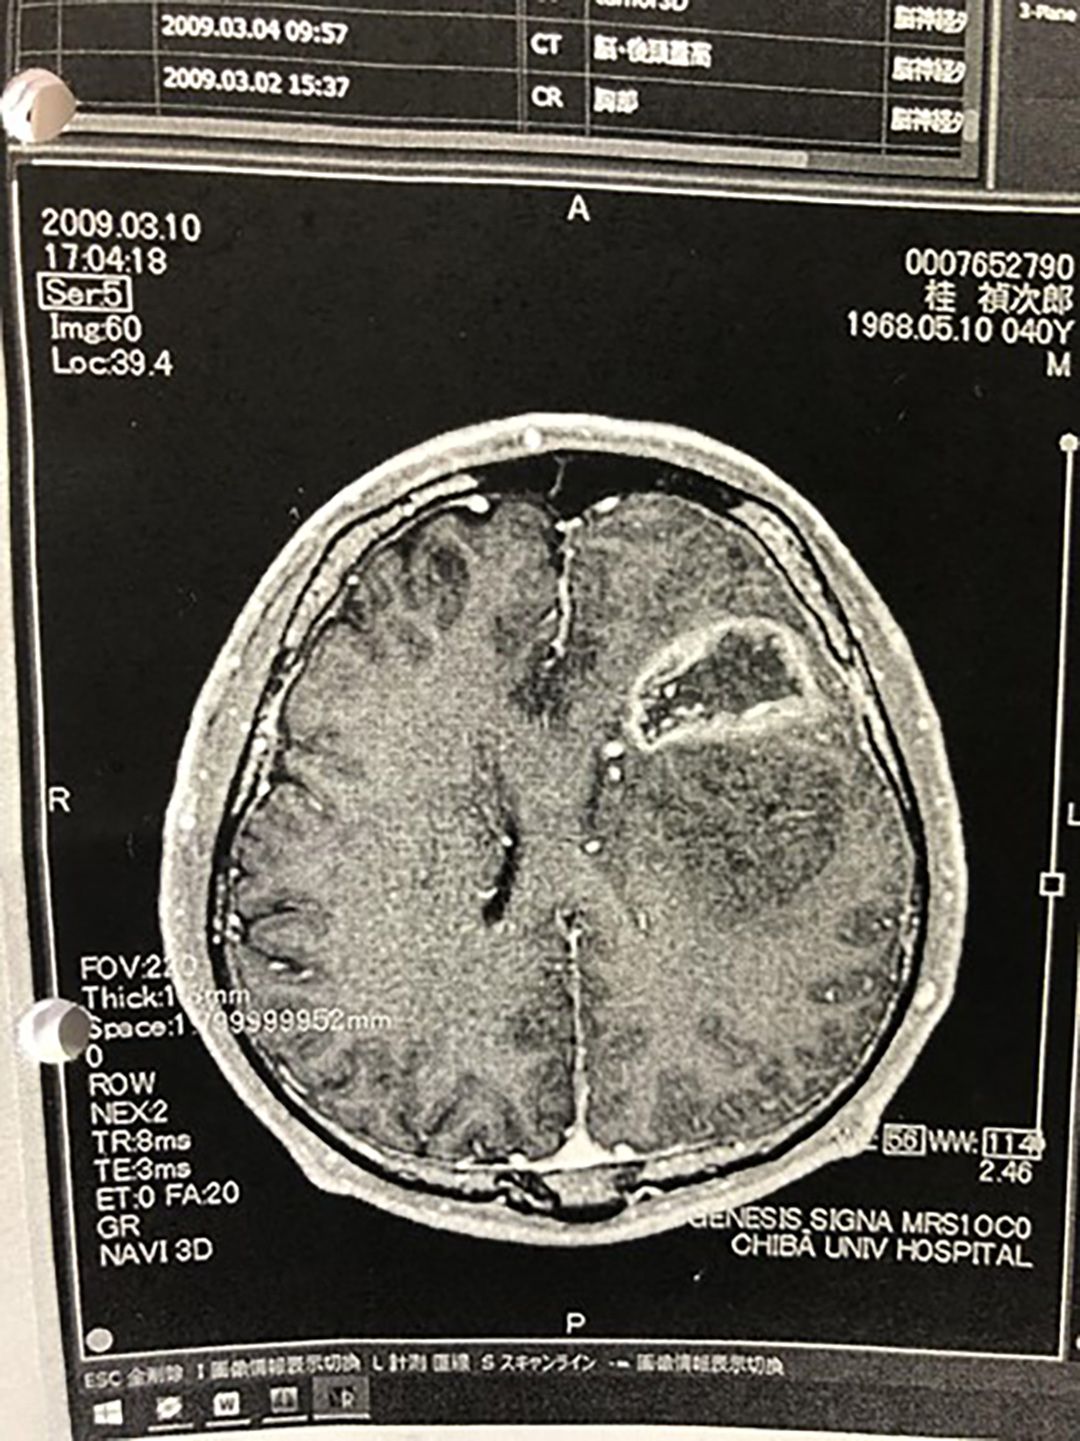

脳の画像は下からとるので左右が逆になる。桂禎次郎の2009年3月10日のMRI画像。左脳にある白い環は「リングエンハンス」といい、膠芽腫の典型的な画像。(写真=『

がん征服

』より)